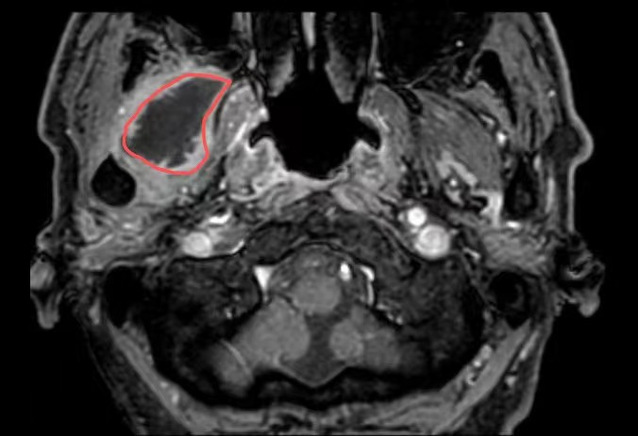

在金沙娱乐城app 超声介入科,徐斌主任就接诊了这样一位患者。一个月前,患者熊先生脸颊部隐隐作痛,到医院一查是牙齿发炎了,抗炎后熊先生拔除了发炎的牙齿。但是,回家后没几天,面颊部就又开始疼痛、发热。经过反复就医、检查、消炎止痛后做增强磁共振提示:右翼外肌及颞肌异常信号,考虑脓肿可能,相关科室的医生和熊先生说这个手术可能比较复杂,需要行开放性手术。

△磁共振提示病灶(红圈处)